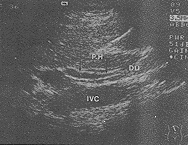

横旋转扫查法多采用平卧位或右侧卧位检查,探头沿胰头体长轴显示胰腺段胆管(C3)横断面,继而以胰头为超声窗,探头右侧端做正负约60°范围内顺、逆时针旋转扫查,以达到连续显示胰头段至末段胆管,以及肝外胆管末端进入十二指肠处。

图2 横旋转法显示C3、C4段胆管

纵旋转扫查法多采用左侧卧位,探头自肝门部向下追踪至胰头,显示其背侧胆管,此时顺时针旋转探头足侧端约30°~60°,使C3、C4得以连续显示(见图1、2)。

图1 纵旋转法显示胆管全程

进入十二指肠(DU)